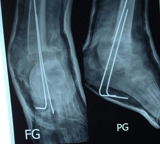

Lange termijn follow-up van een multicenter gerandomiseerde studie betreffende de behandeling van gereduceerde diafysaire antebrachium fracturen bij kinderen.

K.C. Roth, L.W. Diederix, P.P. Edomskis , J.L. Benner, G.A. Kraan, J.H. Allema, M. Reijman, D. Eygendaal, J.W. ColarisNOV Jaarcongres 2022